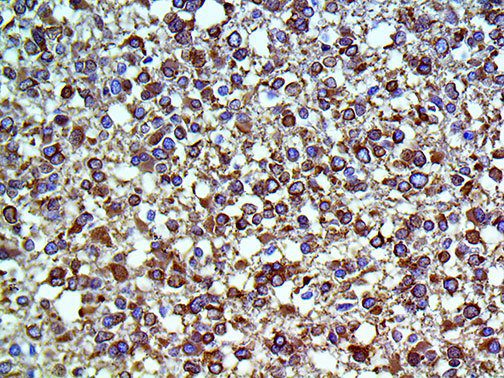

The first cytokines released are interleukin 1β (IL-1β) and tumor necrosis factor-α (TNF-α), which attract a variety of circulating white blood cells (WBCs) to the infection site, including neutrophils, monocytes, macrophages, and natural killer (NK) cells. This response, along with the antipathogenic chemicals released by these cells (i.e., complement), comprise the innate immune response. These cells directly attack the invading pathogen and also release additional cytokines, chief among them interleukin-1 and 6 (IL-6). IL-6 is essential for invoking the adaptive immune response, which calls T-cells, B-cells, and T helper (Th) cells to the infection site. IL-6 also stimulates further recruitment, proliferation and activation of macrophages.

It is the ICU physician who is most likely to witness one of the deadliest manifestations of the abnormal immunological response, the cytokine storm syndrome (CSS). This response is also referred to by some as the cytokine release syndrome (CRS). CSS is characterized by continuous activation and expansion of macrophage and lymphocyte populations, which secrete large amounts of cytokines, causing the cytokine storm. This massive cytokine release is akin to hemophagocytic lymphohistiocytosis (HLH) disease, a syndrome characterized by initial unchecked and persistent activation of cytotoxic T lymphocytes and NK cells.

This activation induces inflammatory monocytes to highly express IL-6, starting a localized and then systemic cascade effect that results in hyperproduction of IL-6, which accelerates the inflammatory process. Because IL-6 also increases vascular permeability, excessive levels cause blood vessels to become very leaky. This, along with clotting factors released from vascular endothelial cells, stimulates the coagulation cascade, resulting in microthrombosis (tiny clots), which leads to ischemia and tissue death of the kidney, intestines, heart, liver, brain and extremities.